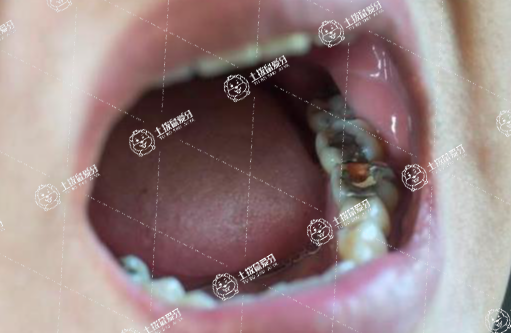

齲齒可以說是臨床上非常常見的一種牙齒問題,當(dāng)牙友們被齲齒所折磨的話,就需要牙友們及時做進(jìn)一步的就醫(yī)處理,避免齲齒給自身身體健康造成更為嚴(yán)重的威脅。補(bǔ)牙可以說是非常常見的一種方式,補(bǔ)牙的填充物一般可以用多久?這或許是牙友們比較在意的事情,接下來,我們一起來了解一下。

補(bǔ)牙齒的填充物一般可以堅持幾年到幾十年左右,具體需要根據(jù)患者補(bǔ)牙后進(jìn)食習(xí)慣以及日常維護(hù)等因素。

患者如果平時喜歡吃較硬以及較黏的食物,可能會導(dǎo)致填充到牙齒的材料出現(xiàn)脫落,這種情況下可能使用的壽命相對比較短,甚至3年到5年就需要更換;反之若平時喜歡吃較軟的食物,對牙齒的損傷相對比較小,填充物使用的時間可能在10年到20年左右。